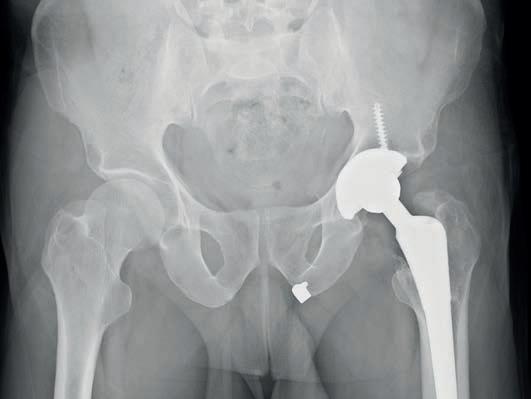

57 Cracking the case: negligence in missed neck of femur fractures

59 Report details the three steps to recovery from hip fracture